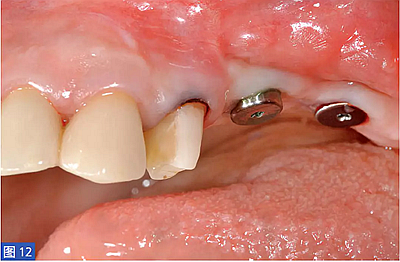

圖12:(右側(cè))病例2. 術(shù)后6個月,2顆種植體植入再生區(qū)域。

在二期手術(shù)中,共植入13顆種植體(病例3中3顆種植體, 其他病例中2 顆種植體)。種植體平均長度為10.2mm( 范圍:6.5-14mm), 直徑4.5mm。平均植入扭矩為32.5Ncm(范圍:25-40Ncm)。植入時,邊緣骨水平為0.94mm(SD:0.45mm)。術(shù)后6 個月, 邊緣骨水平為1.30±0.54mm,產(chǎn)生0.36±0.31mm 的邊緣骨吸收。